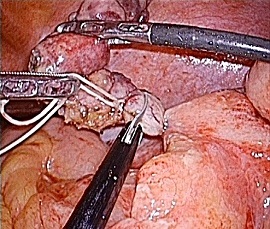

[急性虫垂炎] 手術:腹腔鏡下虫垂切除術(虫垂周囲膿瘍を伴う)

急性腹症のため救急受診。精査の結果、急性虫垂炎と診断。緊急手術(虫垂周囲膿瘍を伴う腹腔鏡下虫垂切除術)を施行した。病理診断結果は急性化膿性虫垂炎であった。

手術画像